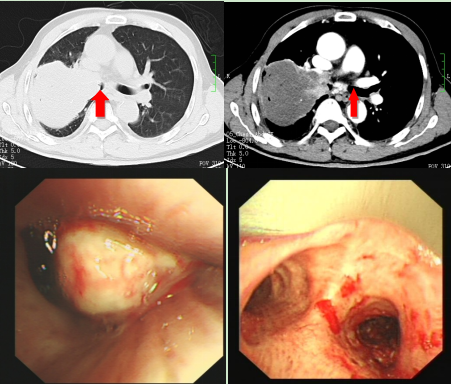

接诊的李秀英副主任医师结合当地医院的检查资料认为,程爷爷右肺有个约10cm的大肿块,由于肿块堵塞了右主支气管,只剩下了一条缝隙,导致其严重的呼吸困难。治疗一方面需要病理确诊肿块的性质,但同时必须要缓解程爷爷的呼吸困难症状,否则老人没有机会进行下一步的抗肿瘤治疗,同时也可能因为阻塞性肺炎、呼吸衰竭而快速死亡。

呼吸介入团队经充分讨论后,决定 “诊断治疗”一步完成。程爷爷入院第二天,吴怀球副主任医师、谭建龙副主任医师在全麻下为其行硬质支气管下右主支气管肿瘤切除术,成功为患者切除右主支气管肿瘤,恢复了大部分的右肺功能。

程大爷在做完支气管镜介入治疗后第二天在查房时对医生说“我已经完全好了,可以回家了”。随后病理结果提示患者是肺鳞癌,经过肿瘤评估之后确诊为晚期肺癌。入院经过呼吸介入治疗后,体力状况明显恢复,气促基本完全缓解,顺利完成肿瘤的全身治疗,于2022年5月30日出院。